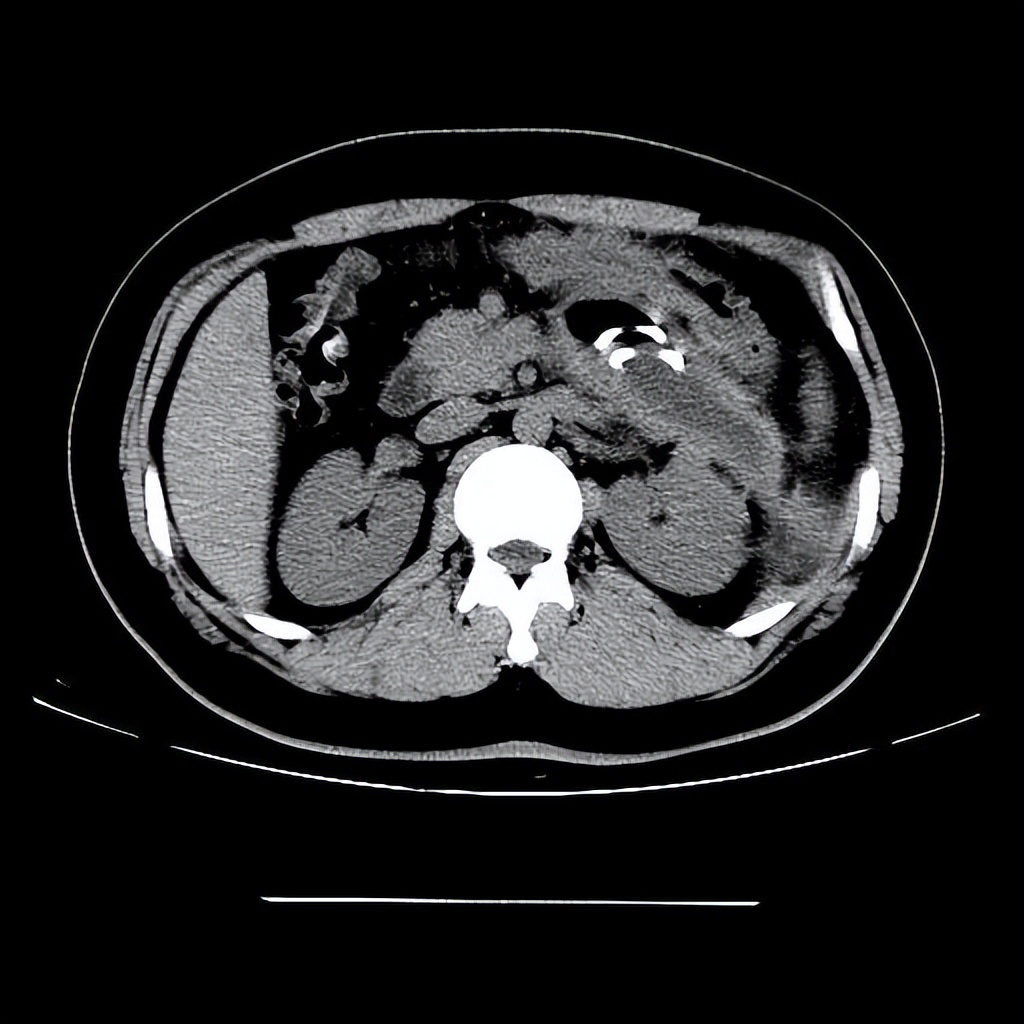

——胰腺囊肿

胰腺囊肿包括真性囊肿,假性囊肿,囊性肿瘤这三种,假性囊肿最为多见,而真性囊肿切除后先少复发。

相比于大多数的良性囊肿,胰腺囊肿的风险是比较高的,如果是胰腺假性囊肿,可能是急性胰腺炎的创伤引起的一个并发症。

而临床发现肿瘤性胰腺囊肿具有着一定的癌变可能,一旦发现胰腺出现的囊肿,就要及早去医院进行相关的检查和干预治疗,否则发生癌变问题的话晚了。

如果是假性囊肿,且体积比较大,要及时进行治疗,如果发生感染可能会引起败血症,囊性肿瘤最大的危害在于可能引起癌变,发现时要及时进行治疗。

——肾囊肿

肾囊肿是肾脏常见的结构异常,大多数肾囊肿不会引起任何症状,当肾囊肿不断变大,此时会出现腰痛。

甚至疼痛会放射到膀胱的部位,并伴有出汗、晕眩、尿血的情况,还会导致尿路堵塞,一般来说,单个肾囊肿很少发生恶变,而且是多发且增厚,肾囊肿会发展肾癌,造成肾功能下降,最终还会发展为尿毒症。

——肝囊肿

在临床上肝囊肿是非常常见的问题,指的是长在肝脏部位的囊肿,随着囊肿数量的增多以及刺激的增大,会容易对肝脏带来严重的损伤。

在复查的过程当中,一旦病情出现恶化或者是发展的速度比较快,体积比较大,甚至已经压迫到了周围的组织和器官,伴随着一些炎症感染,就需要及时的进行手术切除。

而寄生虫性肝囊肿,是指寄生虫在体内循环随着血液到达肝脏慢慢发展,生育形成包虫囊肿,这需要手术治疗,否则会严重损害肝脏。